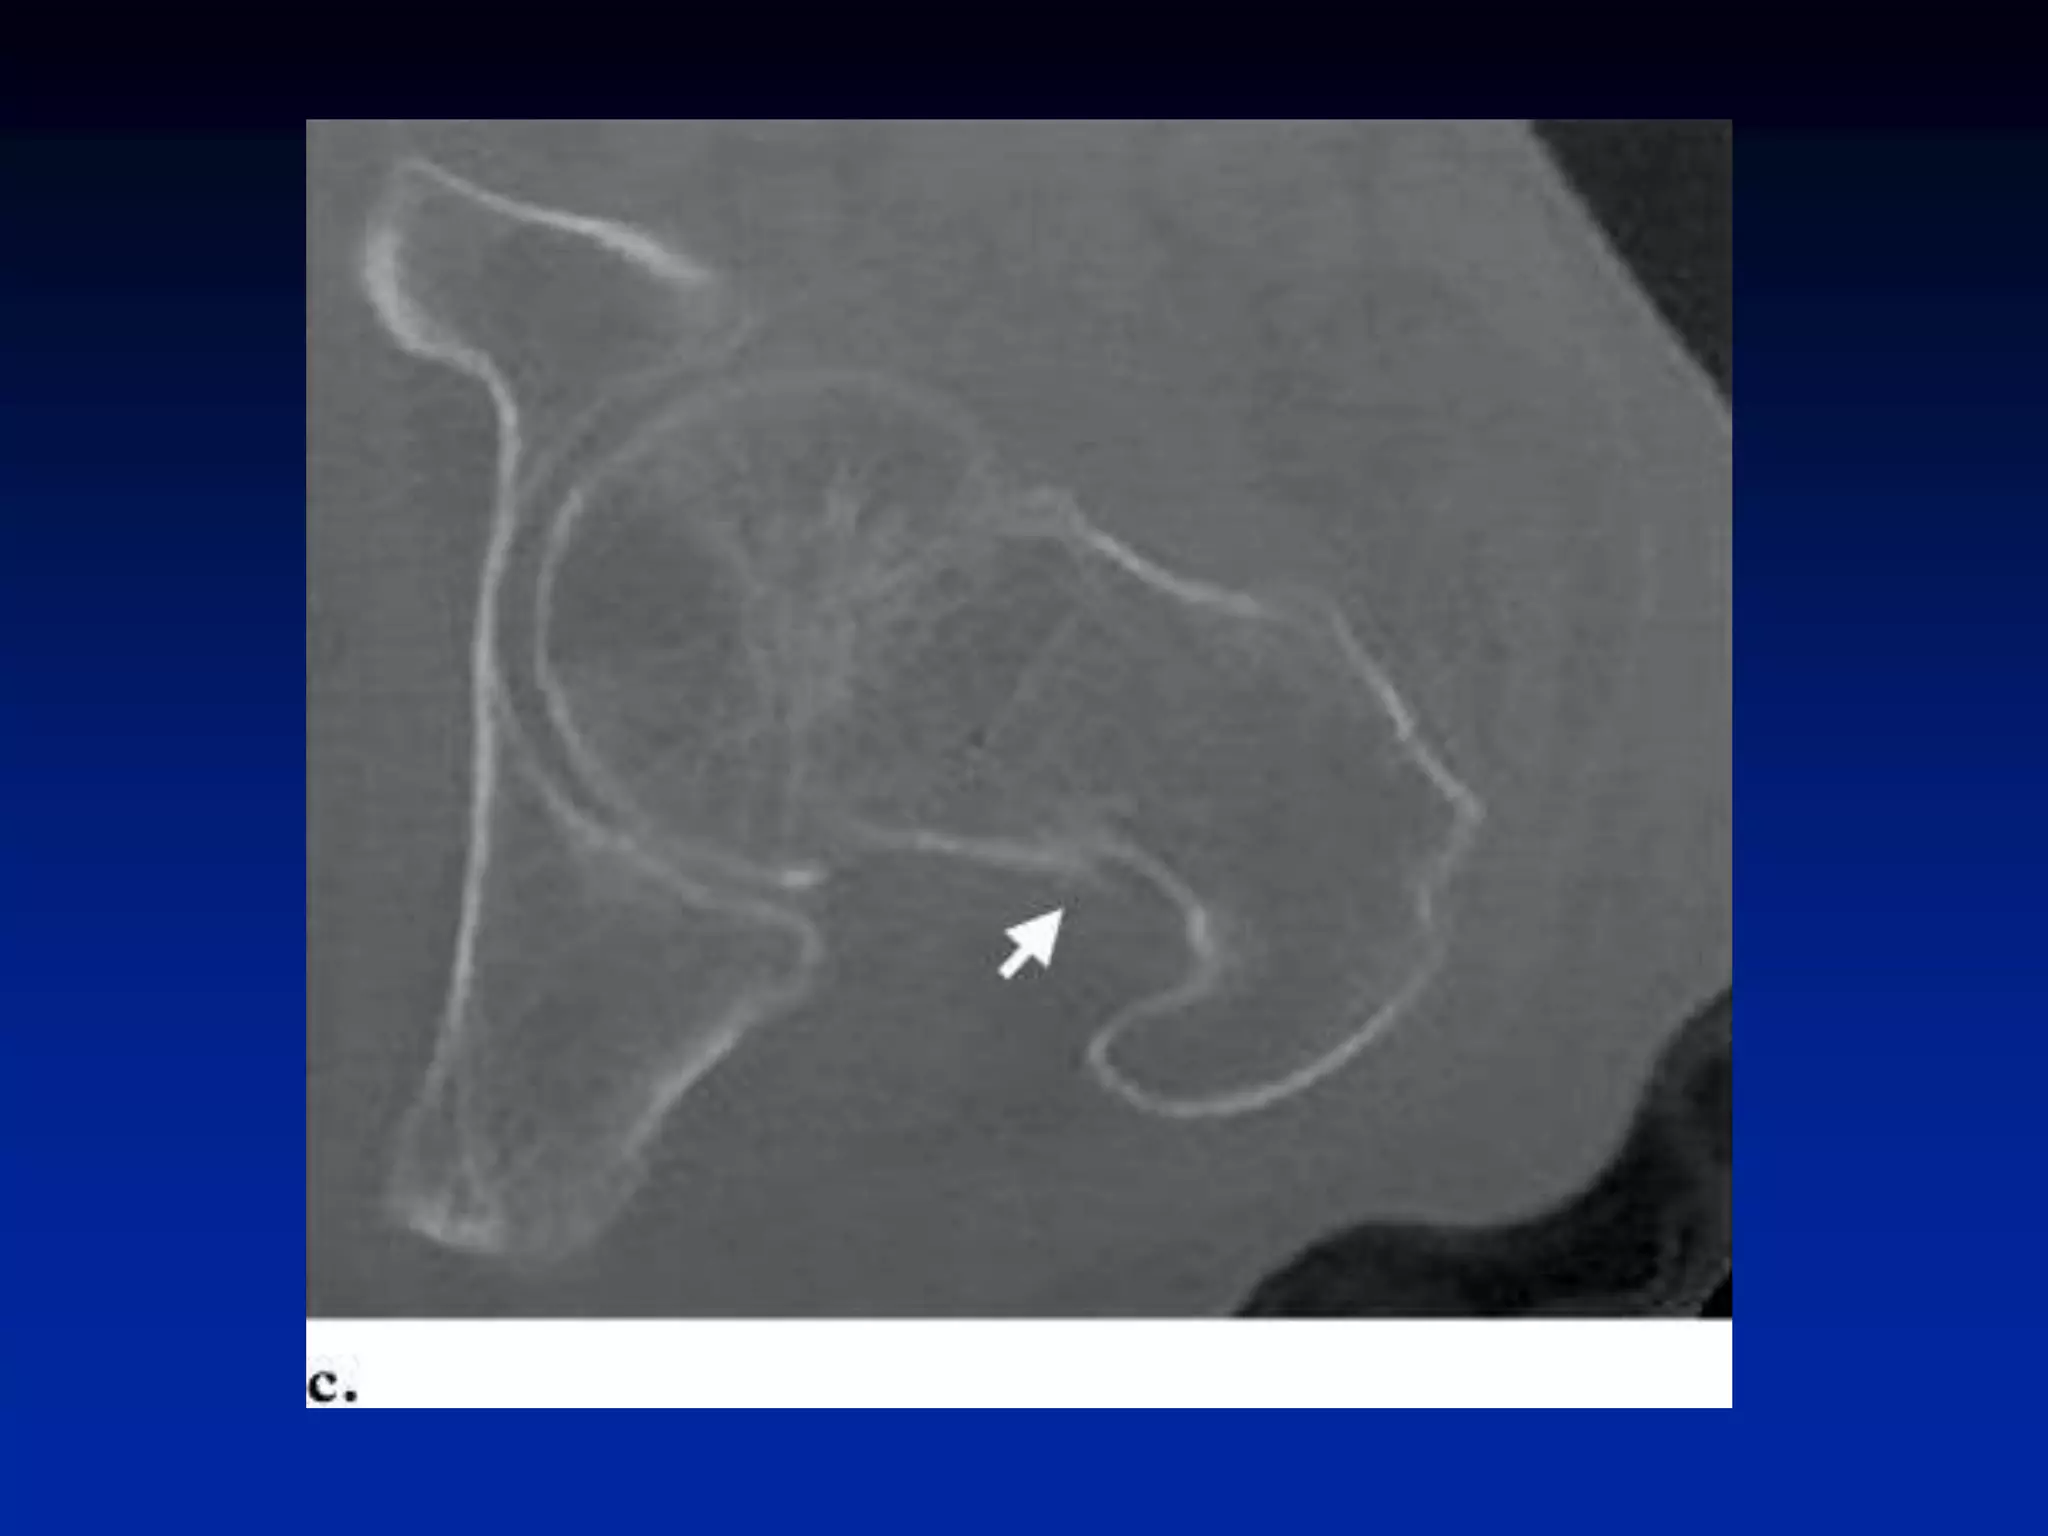

Osteoid Osteoma

– “double density” sign

• 44.

• 45.